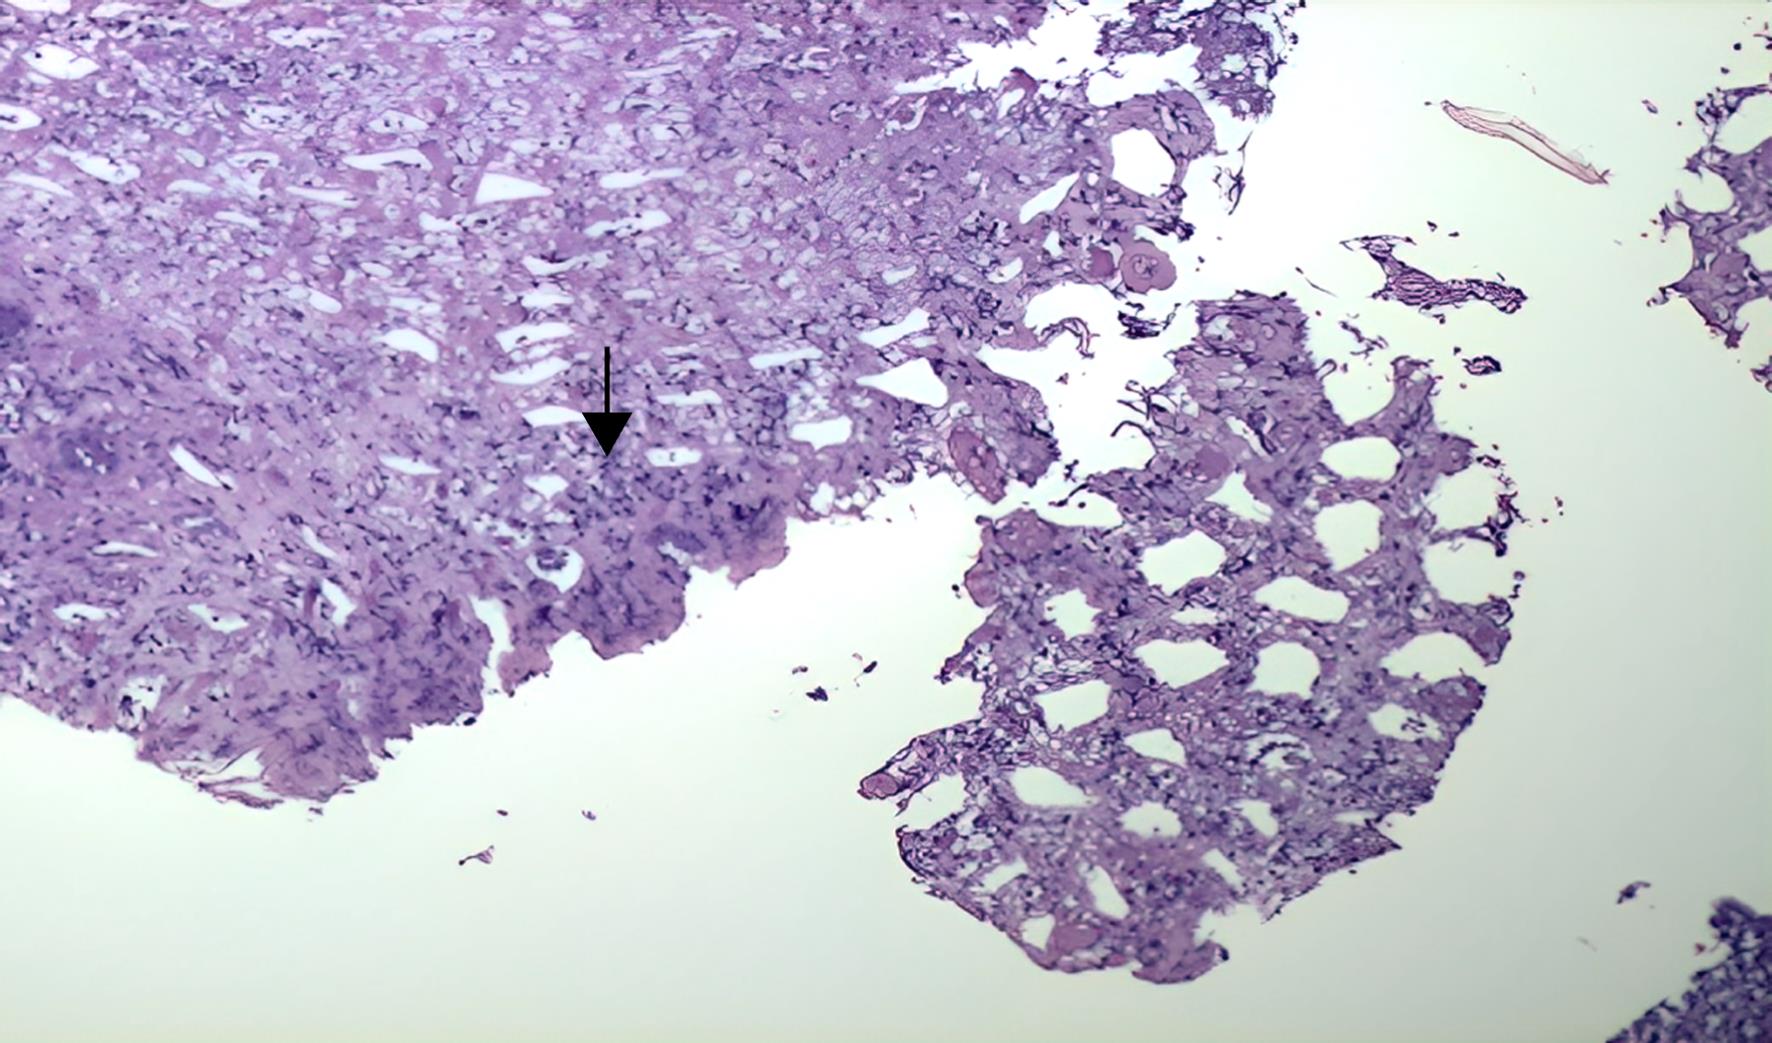

A rectosigmoidoscopy showed ulceration and loss of the normal colonic vascular pattern 30 to 50 cm distal to the anal margin (Fig. 1). Histopathology of the affected area is shown in Figure 2. To rule out conditions beyond the colon, a computed tomography (CT) enterography was performed, which revealed only an inflammatory process in the descending colon (Fig. 3). A colonoscopy confirmed ulceration and inflammation of the colonic mucosa at this site. On the fifth day of hospitalization, the patient experienced another episode of intense abdominal pain and bloody diarrhea one hour after zolmitriptan 2.5 mg was administered for a new migraine episode. After this episode, zolmitriptan was discontinued, and dexamethasone (4 mg intravenous single dose) was initiated. Topiramate was also prescribed, resulting in the complete resolution of the migraine attacks. A neurologic workup for the chronic migraine without aura revealed no organic cause.

Light microscopy (4×) of the affected colonic mucosa stained with hematoxylin and eosin, showing mucosal atrophy and mononuclear infiltrates (black arrow).

Fig. 2  Light microscopy (4×) of the affected colonic mucosa stained with hematoxylin and eosin, showing mucosal atrophy and mononuclear infiltrates (black arrow).